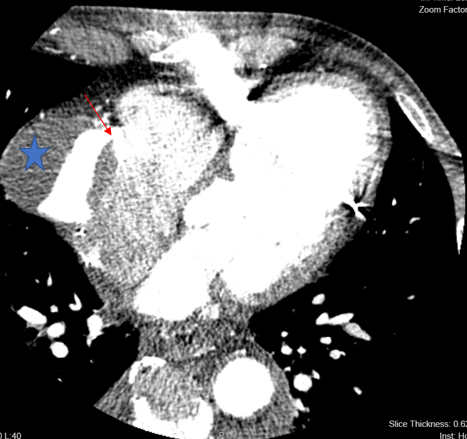

Coronary angiogram showed a large aneurysm in SVG-RCA with a fistula between the SVG to right atrium (RA) (Figure 1, Video). Right heart catheterization demonstrated elevated right-sided and left-sided filling pressures with no step up on oxygen saturation, suggesting bidirectional shunting. However, given the risk of aneurysm rupture, assessment using computed tomography (CT) showed the aneurysm measurements of 5.6 x 5.9 cm in diameter with SVG measuring 8 mm proximal to the aneurysm (Figure 2).1,2 Thallium study was performed and showed no viability in the inferior wall territory.